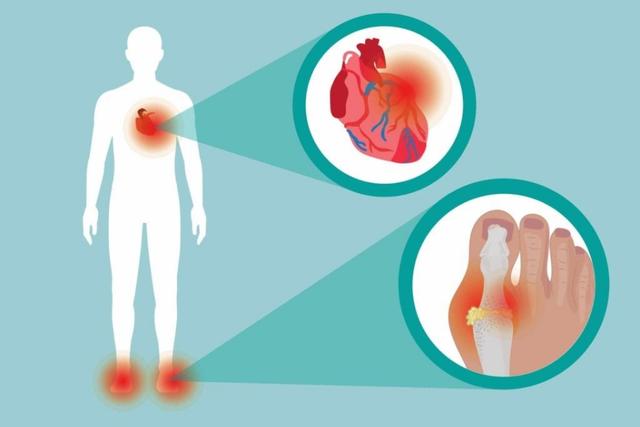

●痛风的发作机制。我们大家都知道,痛风的发作往往都源自于高尿酸血症,正常情况下,我们的血液当中能够容纳的血尿酸浓度不应该超过420,而很多痛风发作的患者尿酸浓度会超过500、600甚至更高。那么当我们体内的尿酸超标以后,就有可能因为尿酸处于过饱和状态而形成尿酸盐结晶,这些尿酸盐结晶是导致痛风发作的罪魁祸首。

通常情况下,距离我们心脏比较远的部位和关节内视尿酸盐沉积比较多的地方,比如肢体远端的关节,像第一足趾关节、踝关节、膝关节、手指以及肘关节都是痛风好发的部位。

- 心血管风险:2017年11月15,美国FDA,发出了一份关于非布司他的心血管风险的安全报告。FDA的报告指出,基于非布司他和别嘌醇的既往临床试验研究结果发现:与别嘌醇(0.6 per100P人/年)相比,非布司他(0.74 per100人/年)的心血管事件的风险更高(心脏病、中风以及心脏相关死亡事件)(这个研究结果也写进了非布司他的说明书)。这个问题我们还是必须要引起重视的,如果痛风的患者本身有心血管方面的问题,那么就不建议口服非布司他或者是要在专业医生的指导下进行服用,而服用药物期间如果出现剧烈的胸痛、明显的呼吸短促、出冷汗、难以控制的恶心和呕吐,无法解释的头晕以及极度的疲劳感,那么请您一定及时停止服药,要到医院寻求专业医生的帮助。